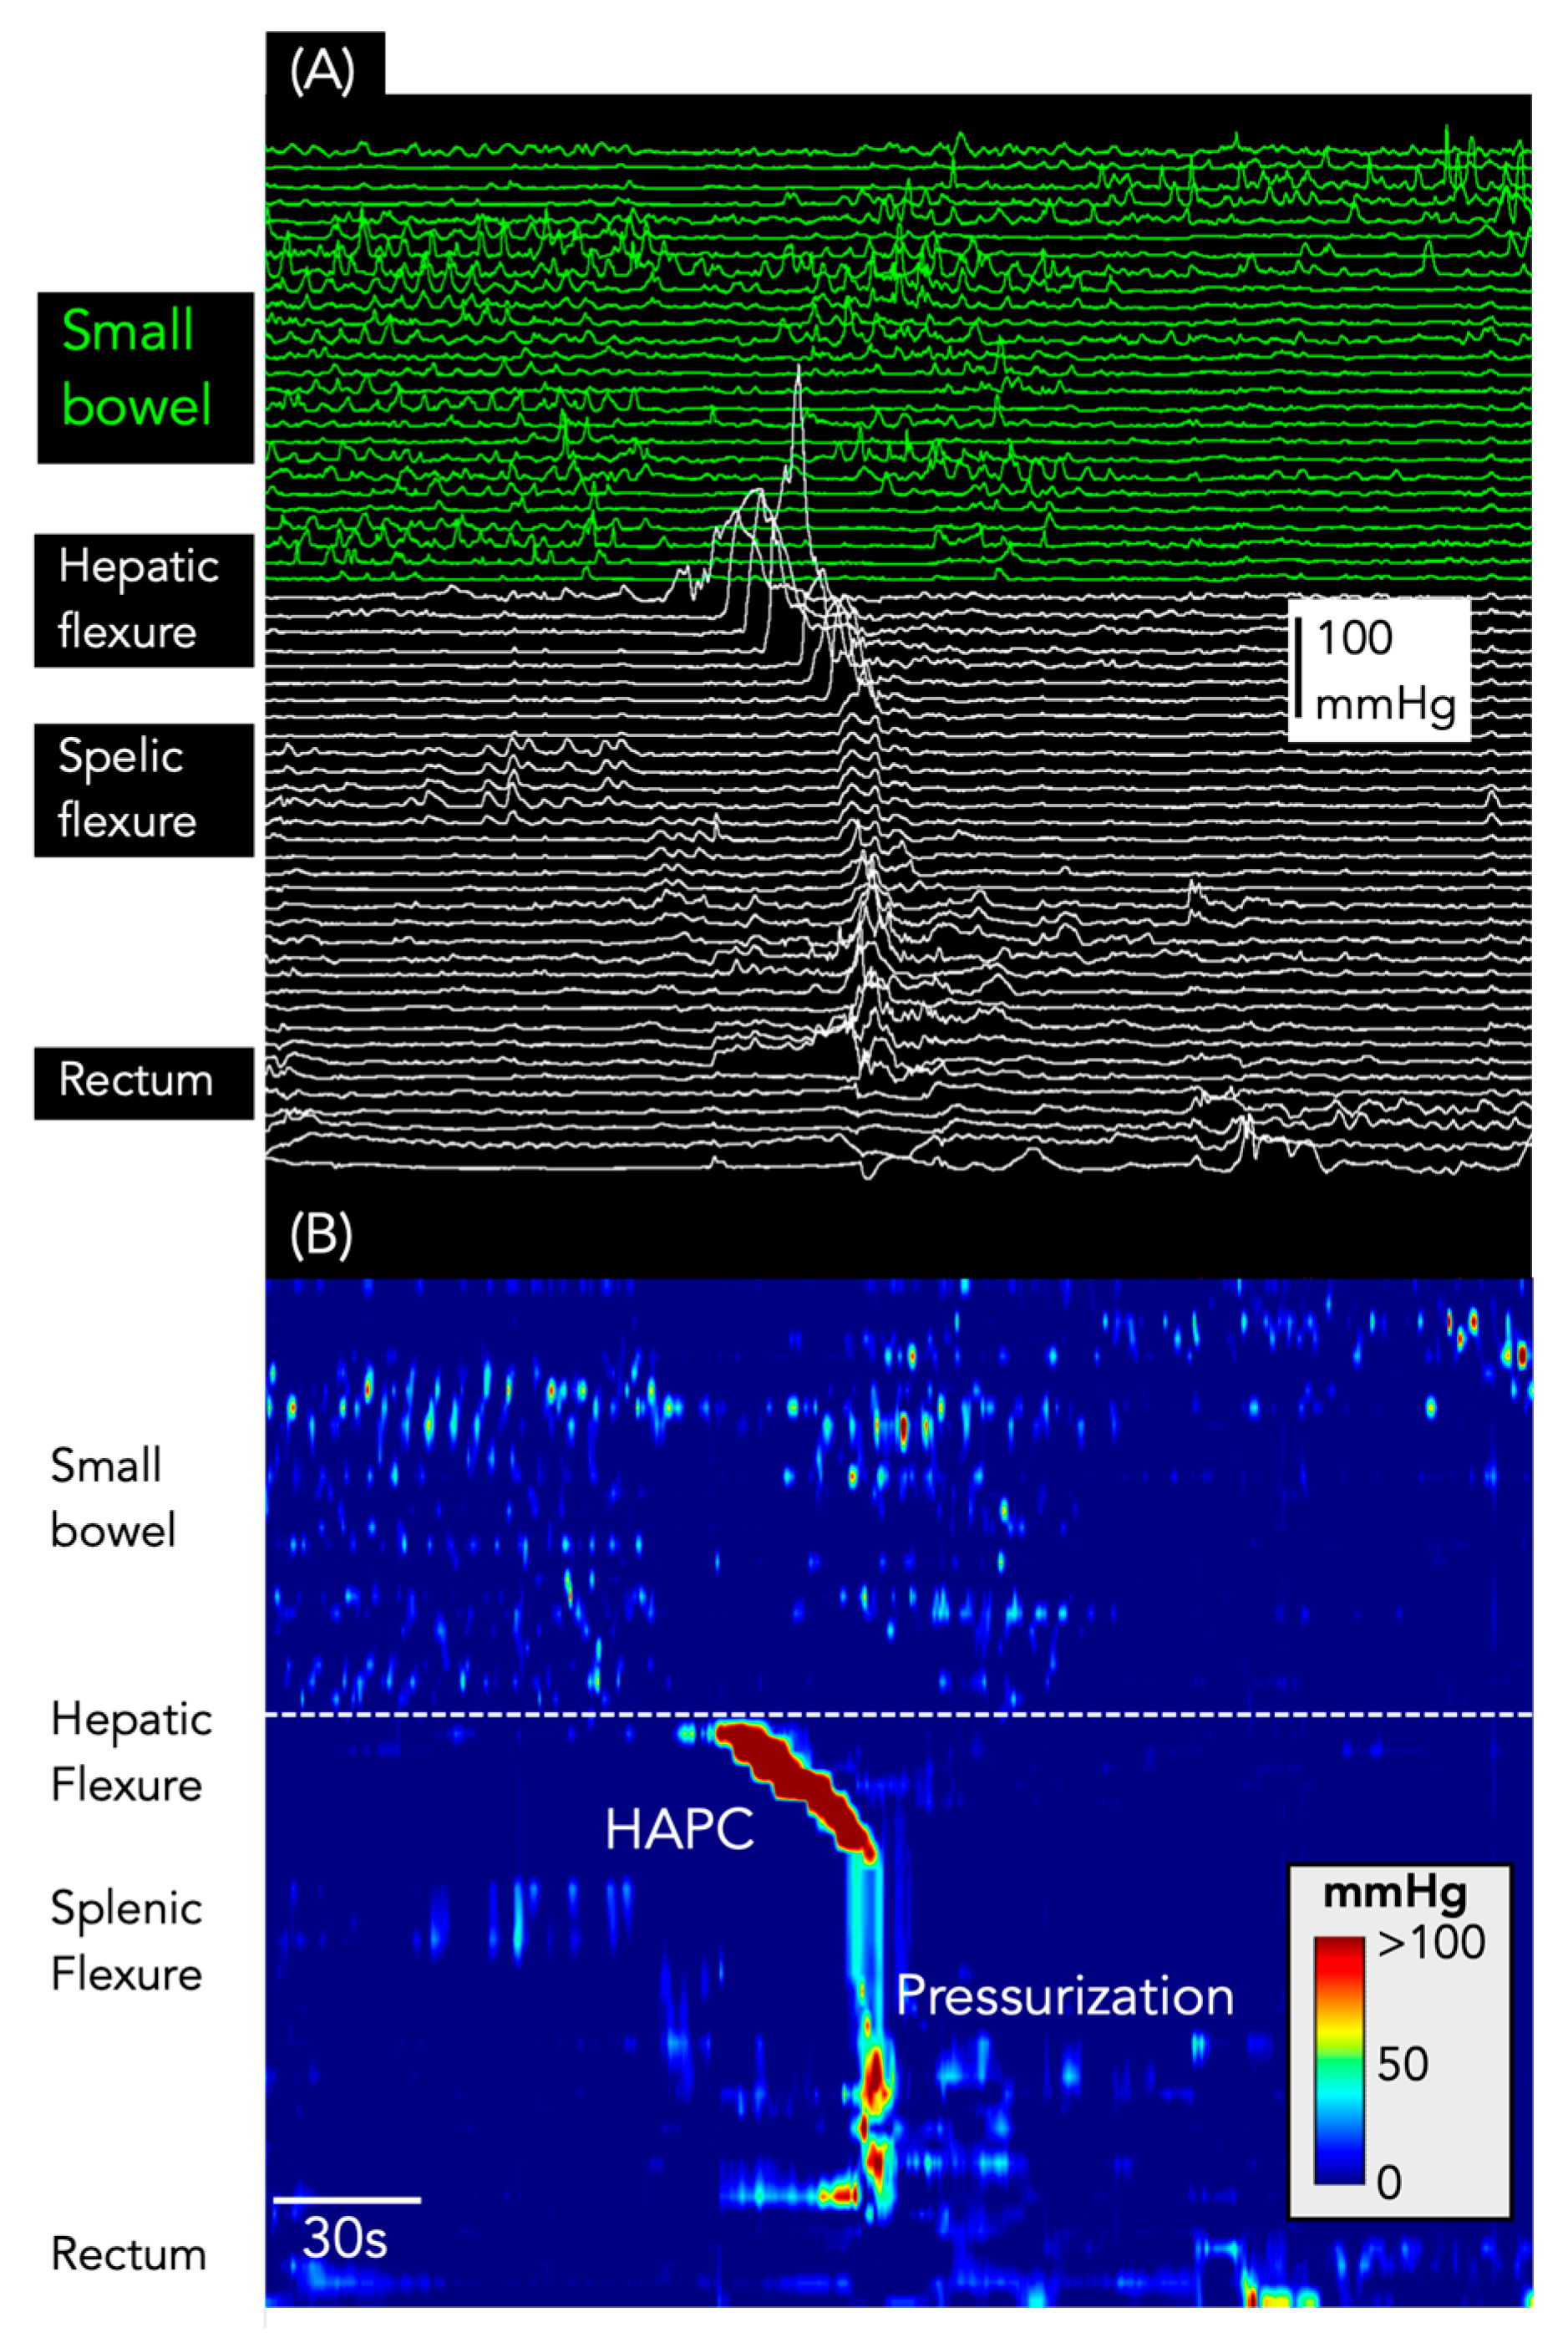

Figure 6.

Pressurizations following a HAPC. (A) shows the line plot of the manometry from the small bowel (green) and colon (white). (B) shows the same data shown as a spatiotemporal colour map.

Pressurizations were associated with 117 HAPCs (36%; Figure 6). Of these, 82 occurred after bisacodyl infusion, 27 occurred in association with HAPCs recorded during the basal period, and 10 occurred after a meal.

In addition to pressurizations, 188/327 HAPCs (57.4%) had SPWs pass through the propagating motor pattern (Figure 7). Every one of these SPWs also spanned all gastric and small bowel sensors (and the oesophagus, if sensors were present in that region: Figure 7).

Figure 7.

Simultaneous pressure waves associated with HAPCs. The X-ray image shows the placement of the catheter in the colon (white circles), small bowel (green circles), and stomach (red circles). The oesophageal sensors are not shown in the X-ray. (A) shows the line plot of the manometry. (B) shows the same data shown as a spatiotemporal colour map. Note that all SPWs span the stomach, small bowel, and colon and, in most instances, they are also detected by the sensors in the oesophagus. All of the SPWs are likely to represent body motion or abdominal strain (artefact) rather than genuine gut contractions.